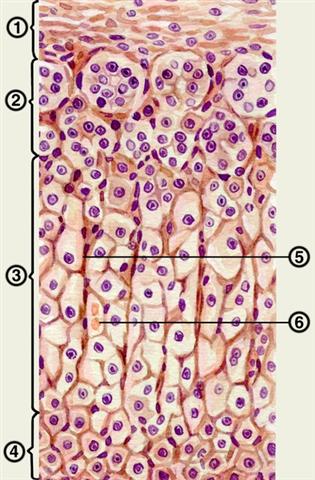

Рис. 2. Гистологическое строение коркового вещества надпочечника: 1 — собственная соединительнотканная капсула надпочечника; 2 — клубочковая зона; 3 — пучковая зона; 4 — сетчатая зона; 5 — соединительнотканные прослойки; 6 — кровеносный сосуд.